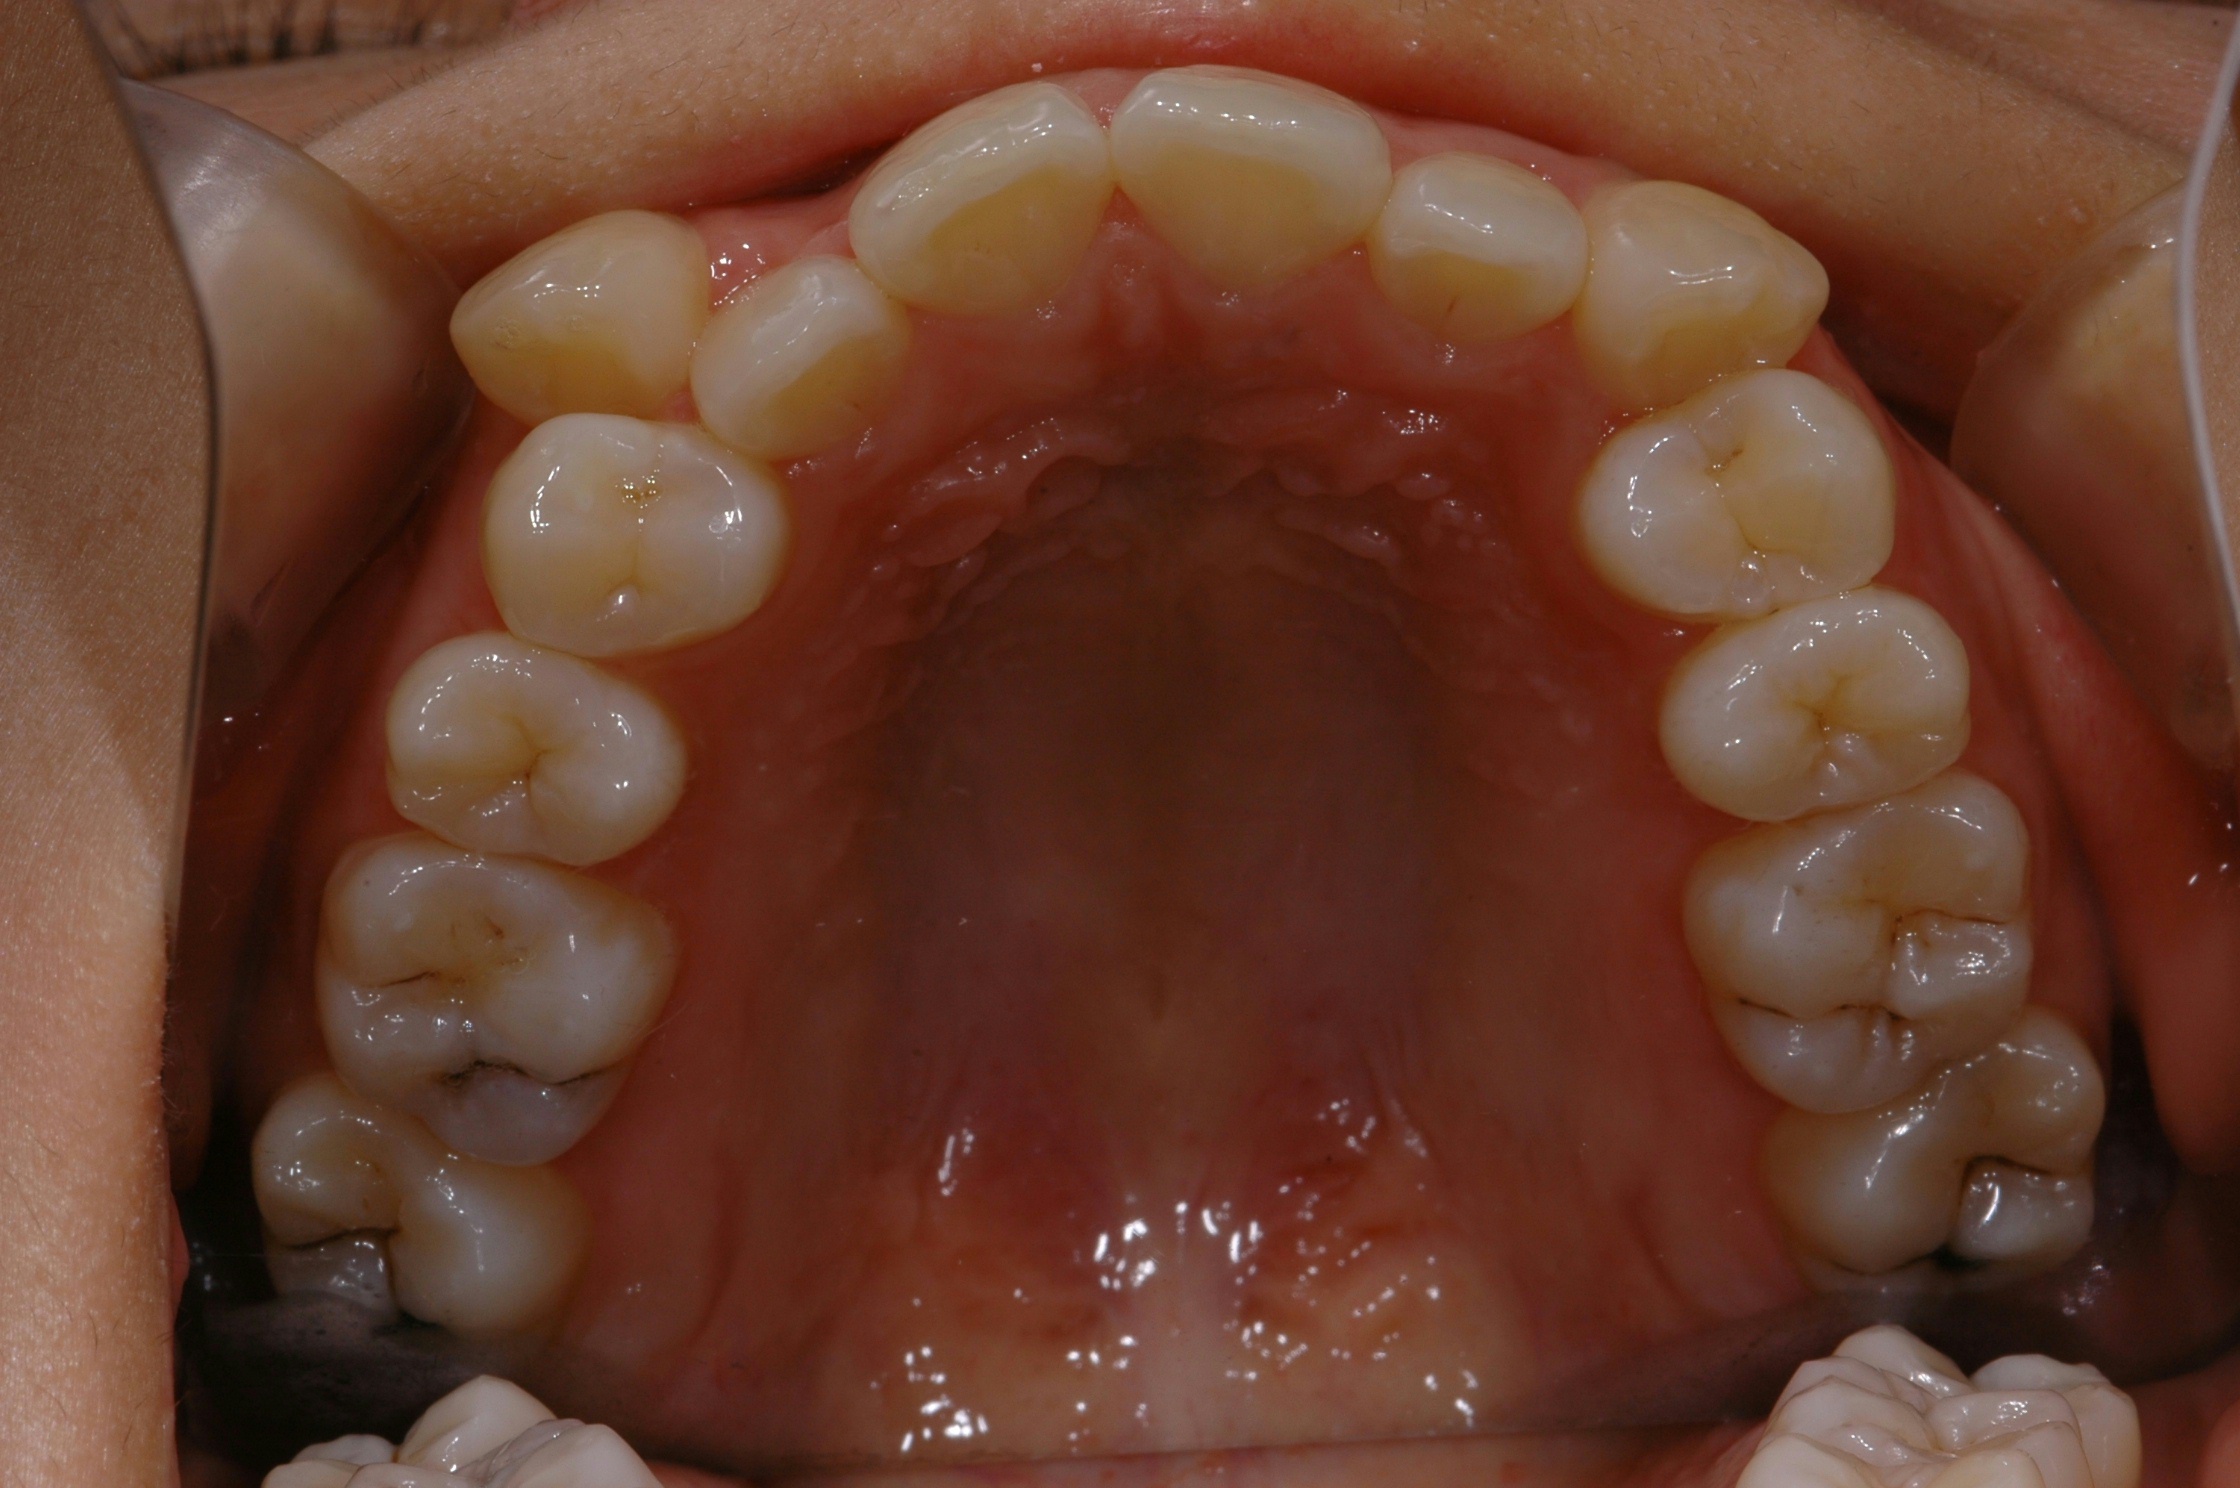

치료 전 사진입니다.